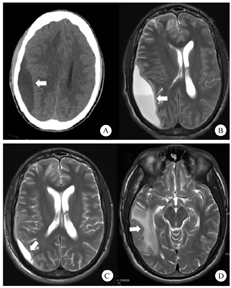

患者男,20岁,赞比亚人,因"发热伴乏力10 d,意识不清2 d"于2019年10月14日收住浙江省人民医院。患者10 d前无明显诱因下出现发热,体温最高达40.8 ℃,伴有畏寒寒战,明显乏力,呕吐、腹泻多次,未行相关诊治。入院2 d前患者出现意识不清,二便失禁,至杭州市临安区人民医院就诊,行血培养提示:麻疹孪生球菌,给予"头孢哌酮钠/舒巴坦钠"抗感染等治疗,病情未见好转,遂至浙江省人民医院就诊。患者既往有疟疾病史,否认近期有局部外伤或侵入性治疗史,否认中耳炎、乳突炎病史。查体:体温40.8 ℃,脉搏104次/min,呼吸23次/min,血压159/136 mmHg(1 mmHg=0.133 kPa)。序贯器官衰竭评分(SOFA)15分。昏迷,双侧瞳孔4 mm,对光反射迟钝,球结膜水肿明显,鼻唇沟对称,颈强直,克氏征阳性,双肺呼吸音粗,双肺散在湿啰音,心律齐,未闻及杂音。腹软,肝脾肋缘下未及,双下肢无水肿,四肢刺痛后能回缩,肌力检查无法配合,巴氏征未引出。实验室检查:白细胞计数(WBC)5.68×109/L,中性粒细胞占比0.906,淋巴细胞0.5×109/L,血小板(PLT)12×109/L,C-反应蛋白(CRP) 257.3 mg/L,降钙素原(PCT)>100 ng/mL;血气分析:酸碱度(pH)7.482,二氧化碳分压22.8 mmHg,氧分压(PaO2) 77 mmHg(吸入氧浓度6 L/min),血氧饱和度94.8%,PaO2/FiO2 171,D-二聚体43 190 μg/L;肿瘤标志物、结核菌素试验(PDD)、HIV检测、血HBsAg、丙型肝炎抗体、登革热病毒RNA均阴性或正常,外周血培养为阴性。头颅CT平扫提示:右侧额颞骨顶部少量硬膜下积液、鼻窦炎。入院当日行腰椎穿刺术,测颅内压>400 mmH2O(1 mmH2O=0.0098 kPa),脑脊液有核细胞计数1 586.0个/μL,红细胞计数52.4个/μL,潘氏试验阳性。脑脊液生化:蛋白定量>3 g/L,糖定量1.53 mmol/L,氯化物118.8 mmol/L,乳酸脱氢酶(LDH)309 U/L,乳酸11.9 mmol/L。脑脊液未找到病原体。初步诊断为:颅内感染、脓毒血症、肺部感染、急性呼吸衰竭。予气管插管呼吸机辅助通气,结合患者病情考虑为细菌感染所致,给予美罗培南(2.0 g/次,1次/d)和达托霉素(0.5 g/次,1次/d)微泵注射及利奈唑胺(0.6 g/次,1次/d)静脉滴注抗菌治疗,甲泼尼龙琥珀酸钠及丙种球蛋白抗炎,甘露醇脱水降颅压等治疗。10月18日行第二次腰椎穿刺术,同时将脑脊液送高通量测序,3 d后结果(武汉华大医学检验所)回报:麻疹孪生球菌序列数28。治疗1周后患者意识转清,但仍有高热及癫痫反复发作。10月22日患者神志清楚,自主呼吸有力,顺利脱机拔管,同时停用达托霉素。11月1日患者突感视物模糊,实验室复查提示:WBC 6.8×109/L,中性粒细胞占比0.671,CRP 77.7 mg/L。复查头颅CT示:右额叶低密度灶,右侧额颞顶枕部硬膜外积液,右侧脑室受压狭窄,中线结构左移(图1A)。11月5日行头颅增强磁共振后提示硬膜下积脓(图1B),11月7日在全麻下行右侧顶部硬膜下脓肿引流术,术中引流出黄绿色液体约40 mL,取脓液培养及进行药物敏感性试验,未检到真菌,术后患者头痛减轻,体温下降。11月9日复查血常规示:WBC 5.02×109/L,中性粒细胞占比0.391,CRP 52.9 mg/L。11月11日,因硬膜下未引流出液体,予以拔除脓肿引流管,脓肿引流液培养阴性。11月12日复查头颅磁共振后患者硬膜下积液再发,但暂无外科处理指征。11月19日患者体温反复,复查血常规示:WBC 8.07×109/L,中性粒细胞占比0.578,CRP 54.1 mg/L。头颅CT示右侧颅内病变较前进展,仍无外科处理指征,抗生素方案调整为利奈唑胺(0.6 g/次,1次/12 h)、奥硝唑(100 mL/次,1次/12 h)及美罗培南(2 g/次,1次/8 h)联合治疗。12月5日,因患者近期体温均正常,头痛明显好转,调整为利奈唑胺(0.6 g/次,1次/12 h)联合头孢曲松钠(2 g,1次/12 h)抗感染治疗。12月29日复查血常规:WBC 5.57×109/L,中性粒细胞占比0.453,CRP 10.4 mg/L。2020年1月3日复查头颅平扫磁共振提示:硬膜下脓肿较前减小,右侧大脑半球多发异常信号(图1C,图1D)。病情趋于平稳,体温控制在36.9 ℃左右,头痛乏力等症状较前明显改善,嘱其继续口服利奈唑胺抗感染治疗,出院6个月后电话随访,未再发热,一般情况好转。

注:A.右侧额颞顶枕部硬膜外积液,右侧脑室受压狭窄,中线结构左移;B.右侧硬膜下积脓;C.脓肿引流和抗生素治疗近2个月后脓肿缩小;D.右侧大脑半球多发异常信号